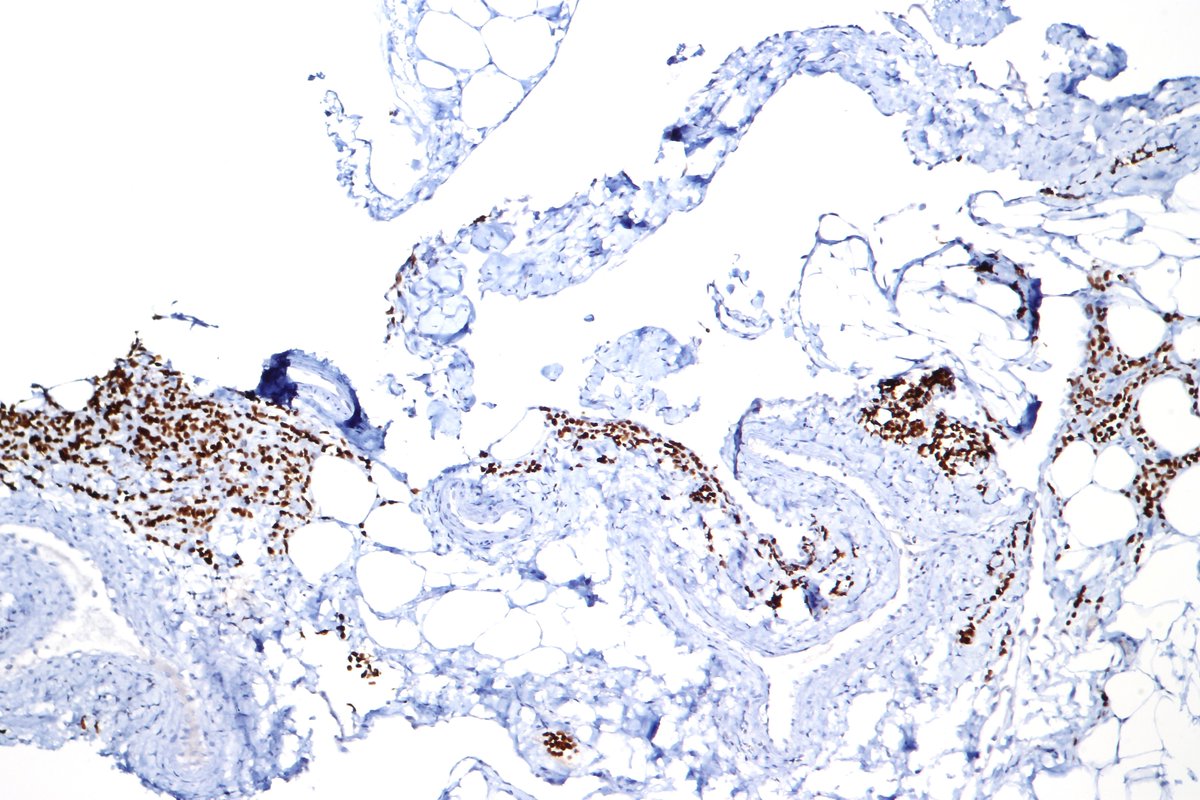

Fetal testis (14 weeks) showing primitive tubules with germ cells surrounded by interstitial Leydig cells. #pathology #pedipath